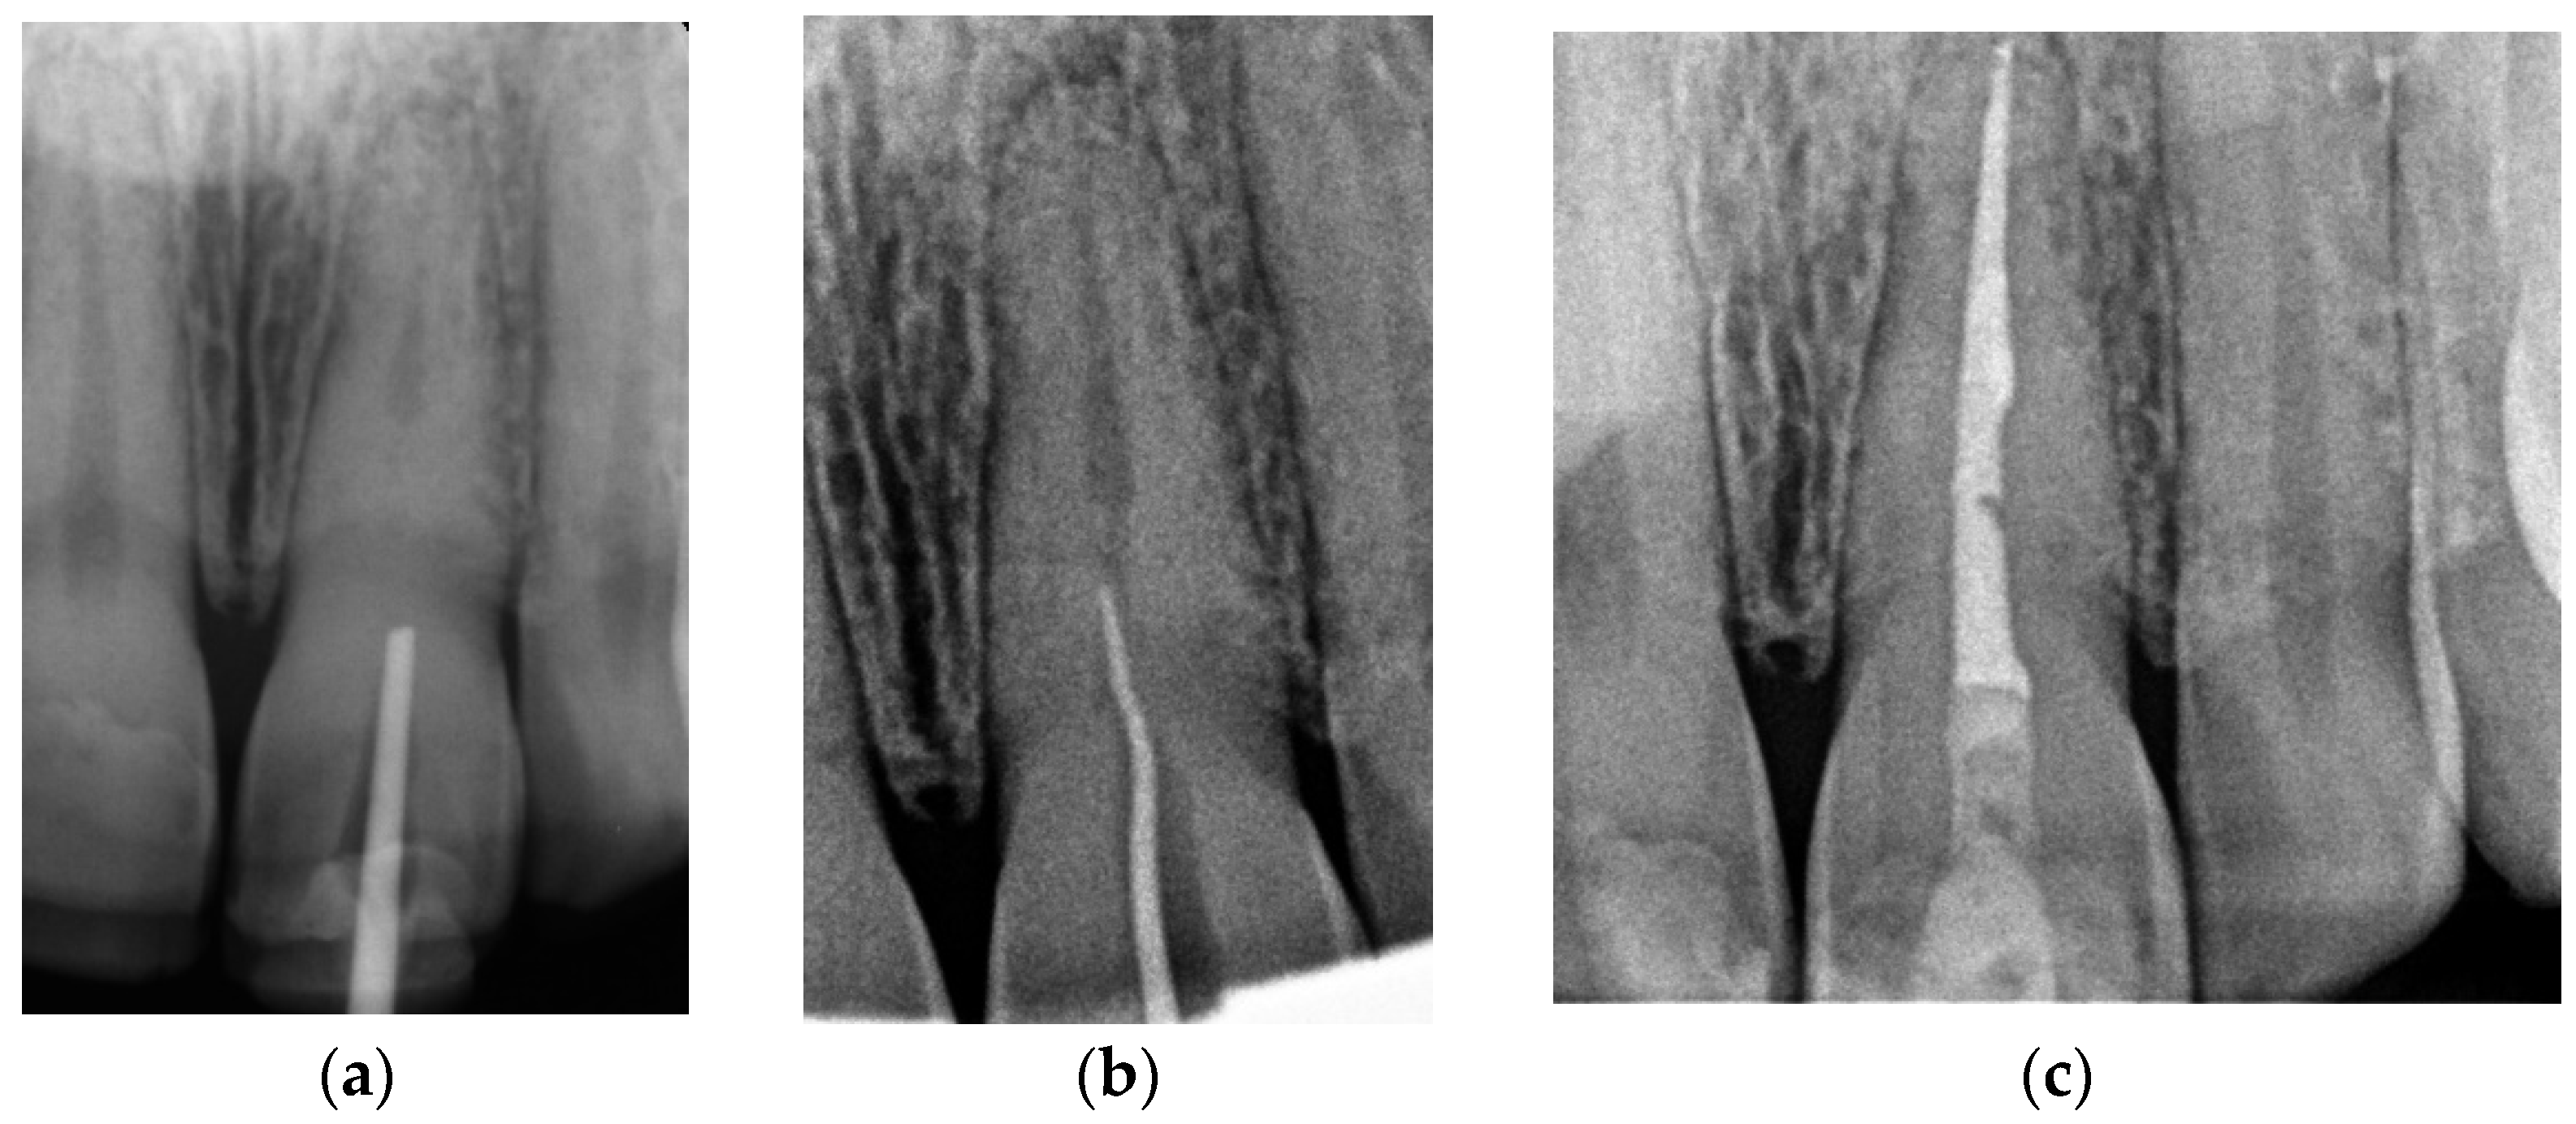

2.1.1. Case Report—Patient A: Symptomatic Pulp Necrosis after Trauma

Three-Dimensional Treatment Plan

Canal Treatment

2.1.2. Case Report—Patient B: Asymptomatic Pulp Canal Obliteration after Trauma in Tooth Requiring Prosthetic Treatment (Aesthetic Dental Crown)